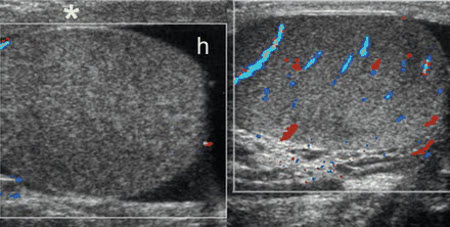

Torção testicular: imagens bilaterais transversais com Doppler colorido em um menino de 12 anos com dor escrotal do lado direito, de início súbito, sem sinais de fluxo colorido no testículo direito, que está aumentado e tem ecogenicidade heterogênea; hidrocele reativa (h) e espessamento da parede escrotal (*) também são observados; torção testicular e deformidade em badalo de sino foram confirmados no momento da cirurgia

Aso C, et al. Radiographics. 2005 Set-Out;25(5):1197-214; usado com permissão